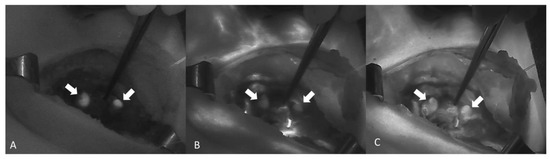

| (Roland Ladurner et al., 2019) [59] | AF and exogenous | ICG-Pulsion | 5 mg | After lateral mobilization of the thyroid gland | Storz laparoscopic NIR/ICG imaging system |

| (Roland Ladurner et al., 2019) [59] | In total, 179 PGs (87.3%) displayed NIRAF showing a typical bluish violet color. | Not measured | Not measured |